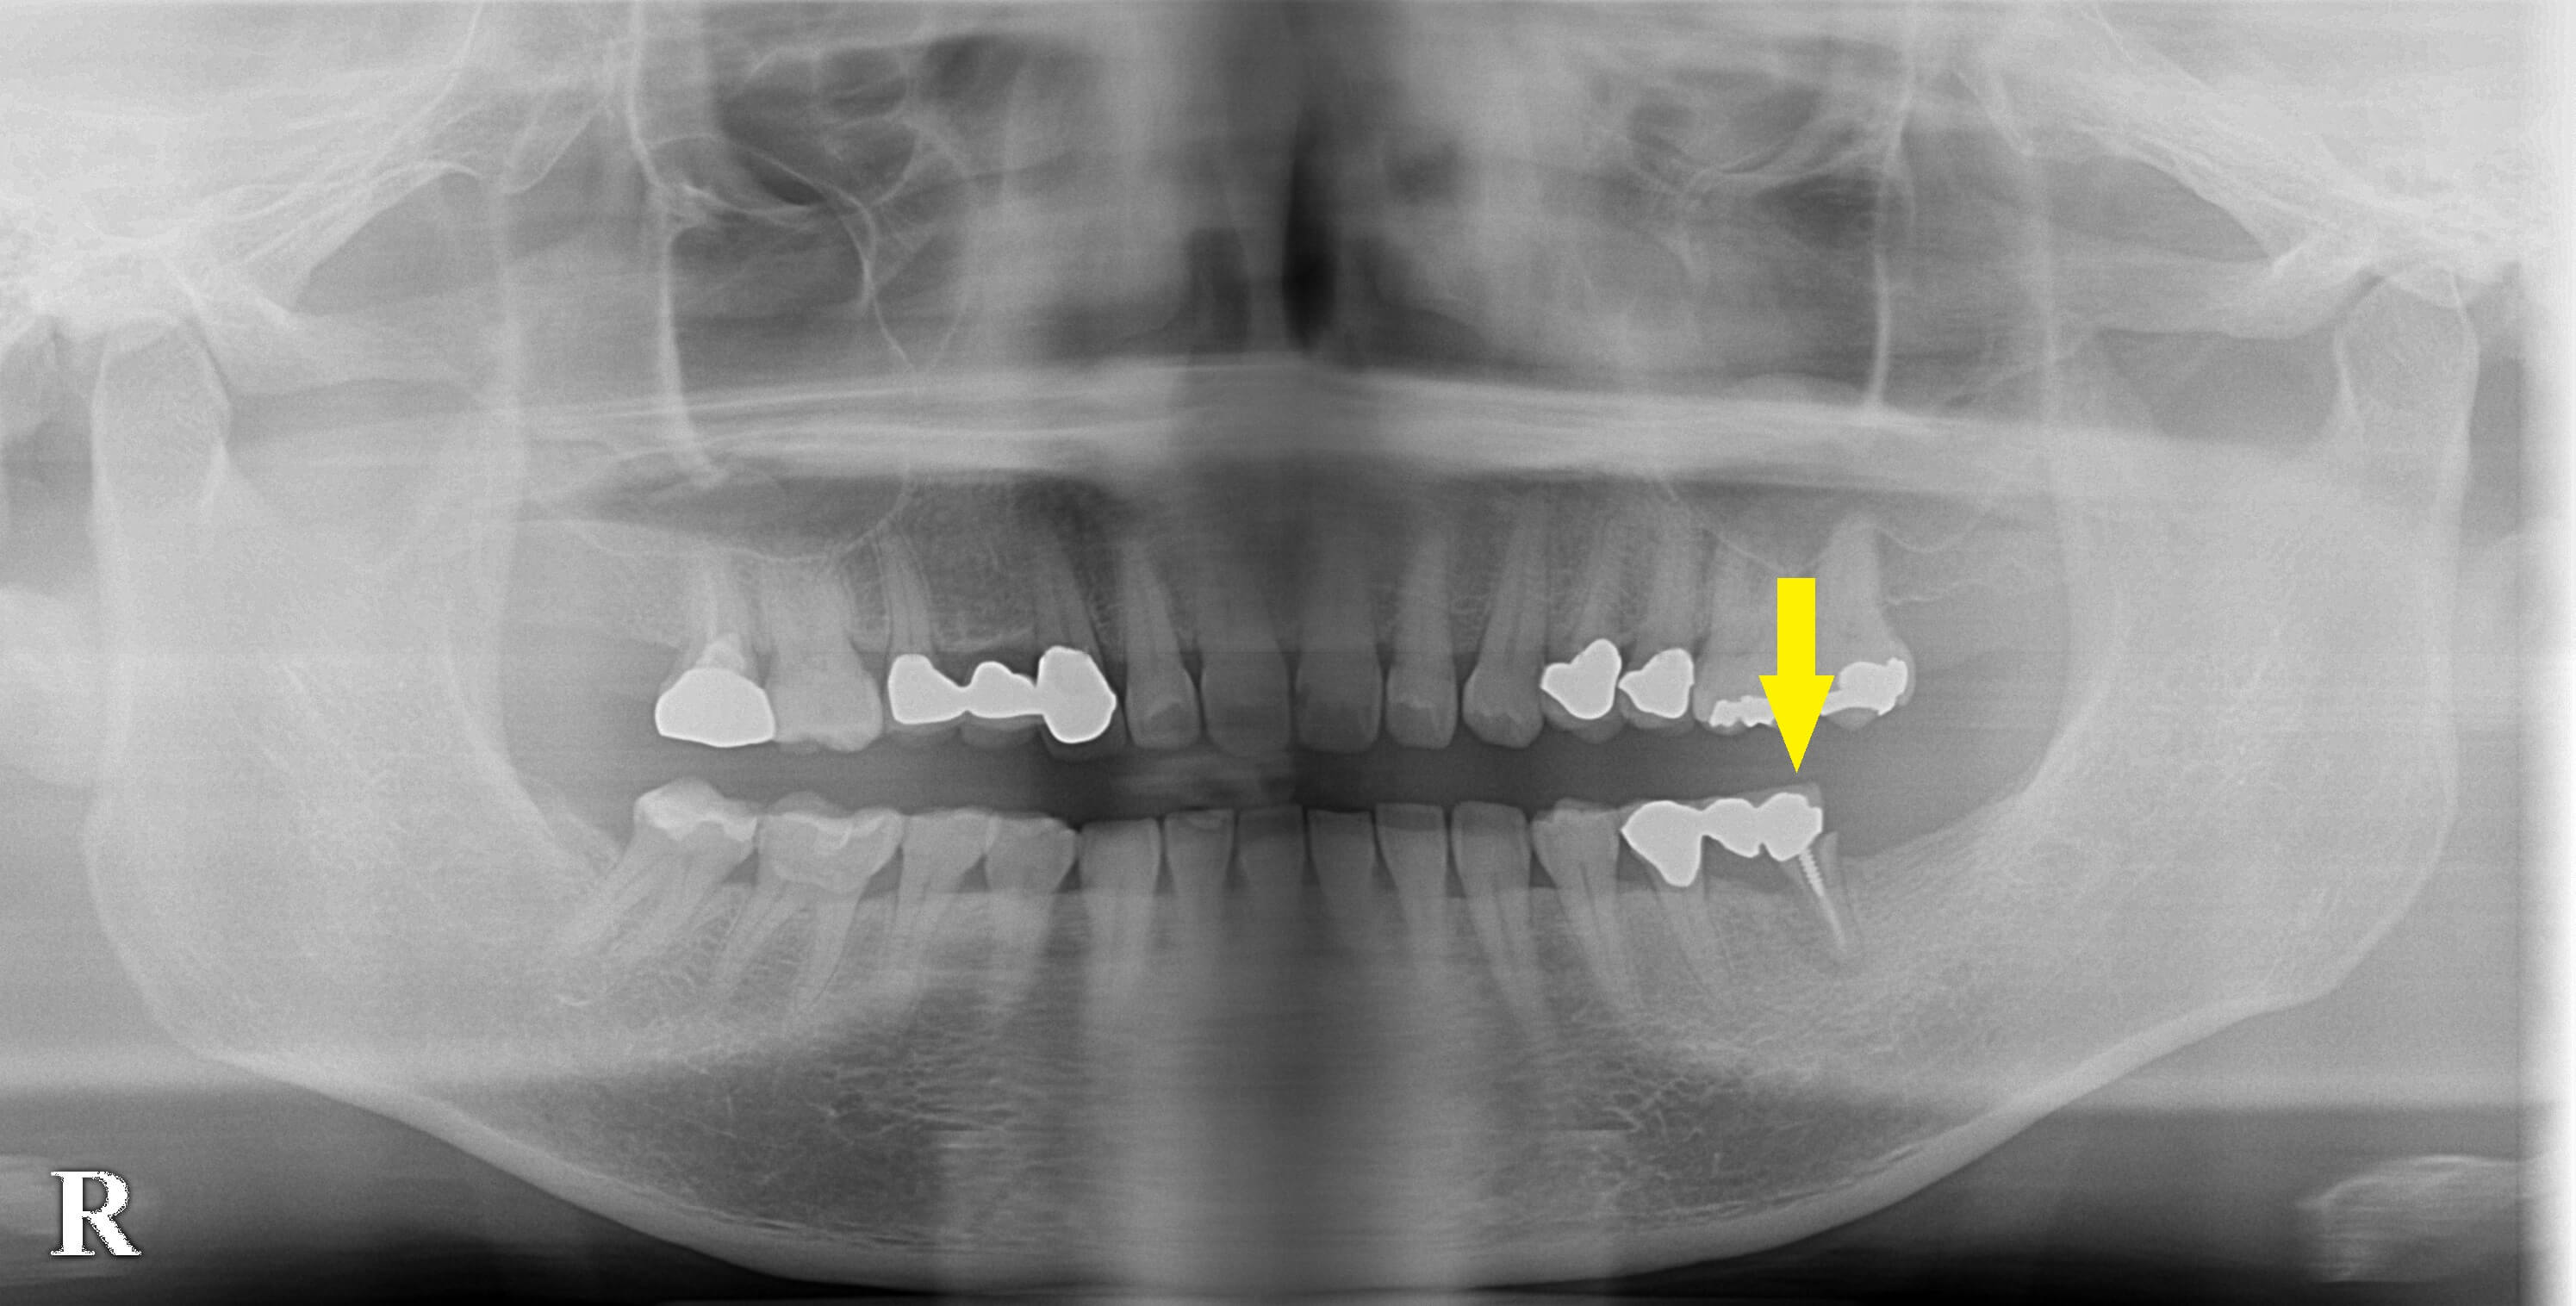

左下顎の臼歯部がブリッジとなっていたのですが、最近になって違和感があったためかかりつけの歯科医院を受診したところ、ブリッジの支えになっている歯が破折していて、抜歯しなければならないと言われたそうです。

ブリッジの支えの1歯は抜歯して、ここに2本のインプラントを埋入し、大臼歯2歯を回復することで同意されました。